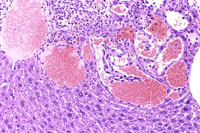

This hemangiosarcoma is well demarcated from the normal hepatic parenchyma; sharp demarcation is an unusual feature of hemangiosarcomas. Large blood-filled lakes are apparent. Higher magnification shows bands of spindle-shaped endothelial cells with attendant destruction of hepatocytes, proliferation of plump endothelial cells, and atrophy of hepatocytes.